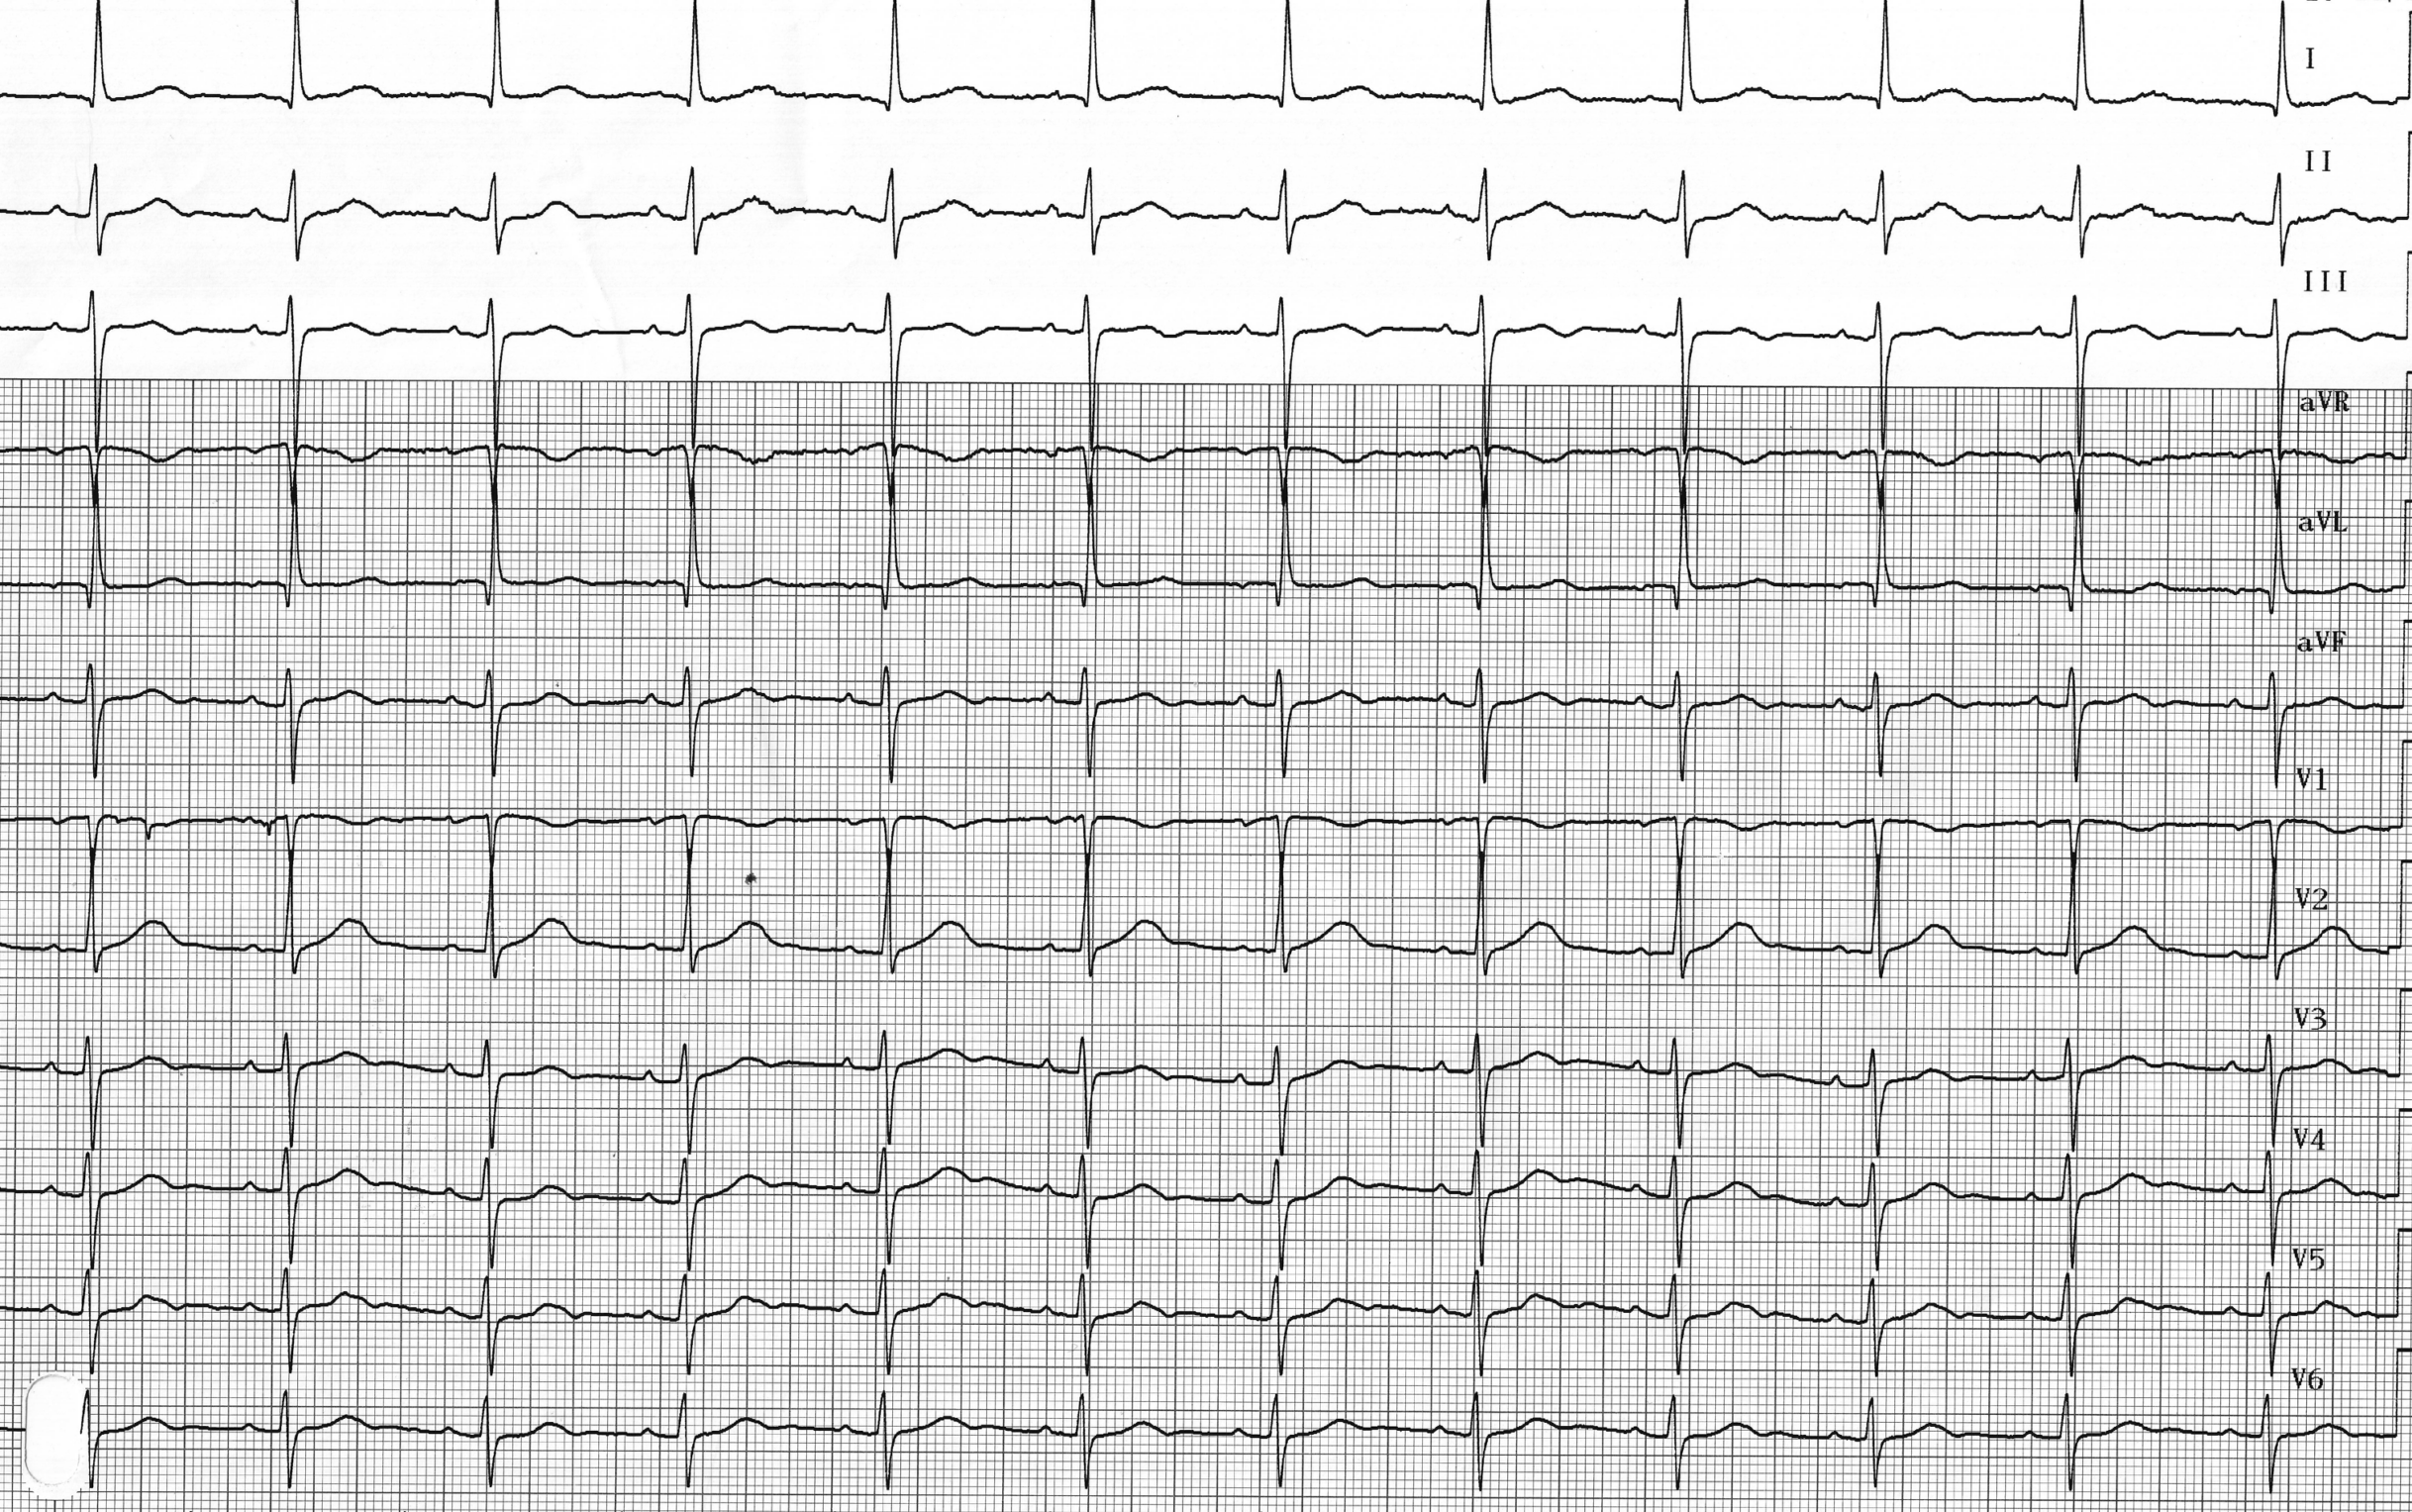

Description tracé

Il s’agit ici de l’enregistrement (simultanément au tracé précédent) des électrogrammes endocavitaires à partir du programmateur; l’EGM 3 correspond à une dérivation électrocardiographique, l’EGM2 à l’EGM ventriculaire et l’EGM1 à l’EGM atrial; activités atriale et ventriculaire spontanées (AS-VS);